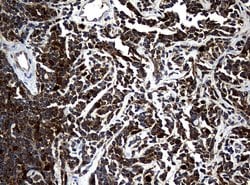

| Immunocytochemistry, Immunofluorescence, Immunohistochemistry (Paraffin) | |